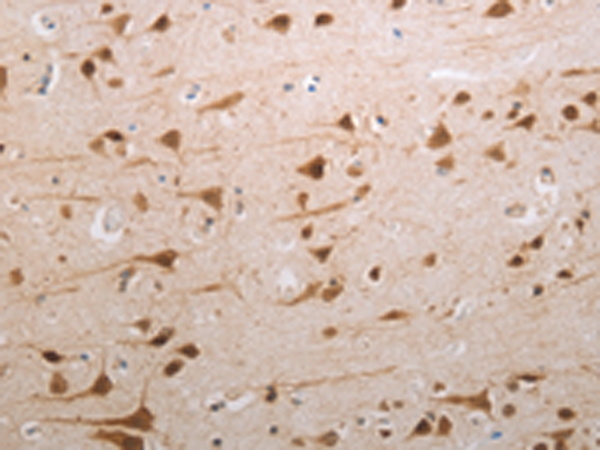

分类: 科研抗体货号: P04322别名: APH; OPH; AARE; ACPH; D3S48E; D3F15S2; DNF15S2应用: WB,IHC反应种属: Human, Mouse, Rat